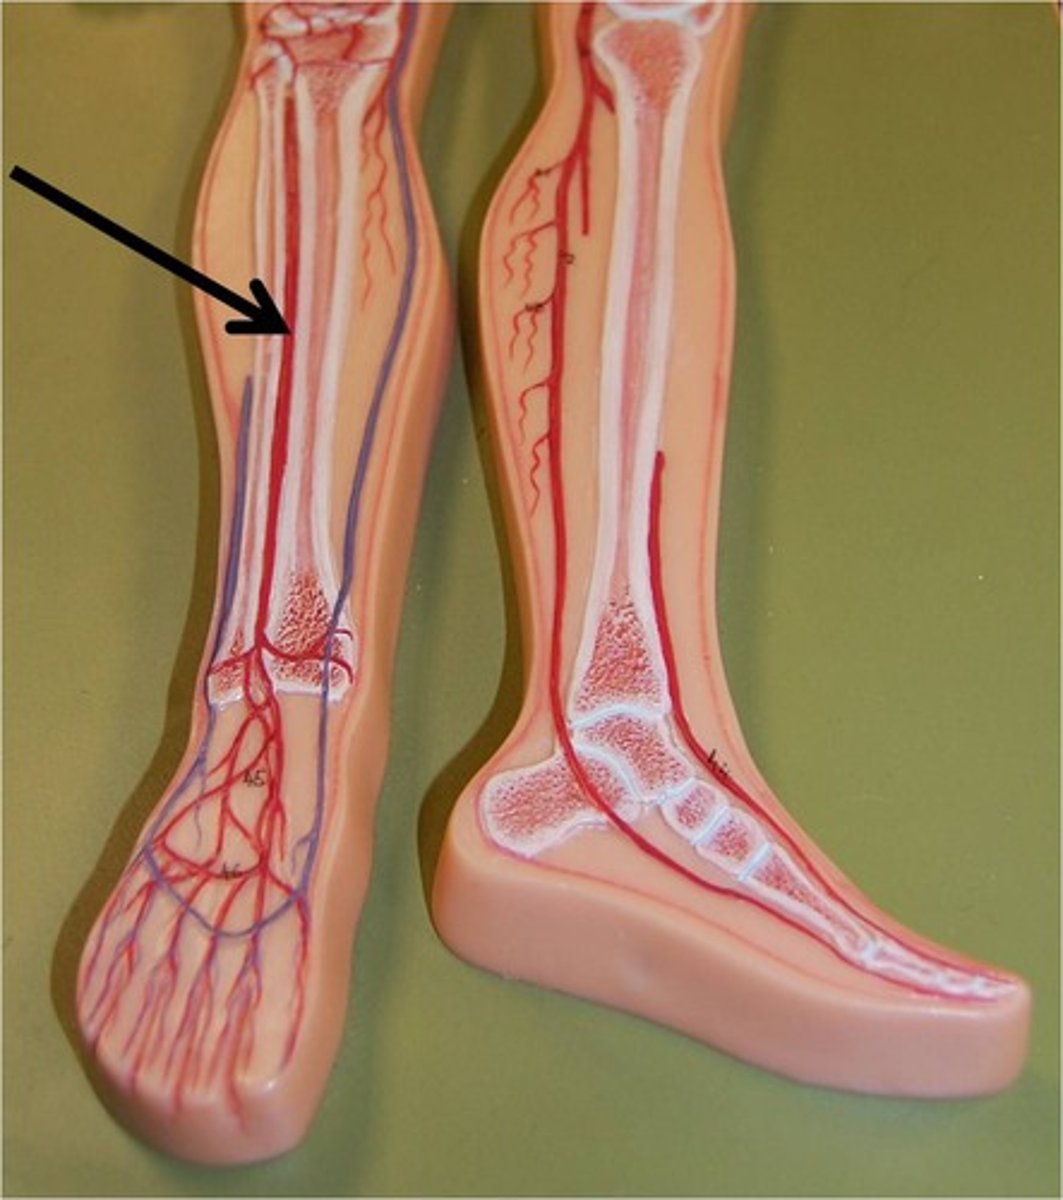

anterior tibial artery

serves the muscles in the anterior compartment of the leg

posterior tibial artery

serves the muscles in the posteromedial part of the leg

anterior tibial vein

posterior tibial vein